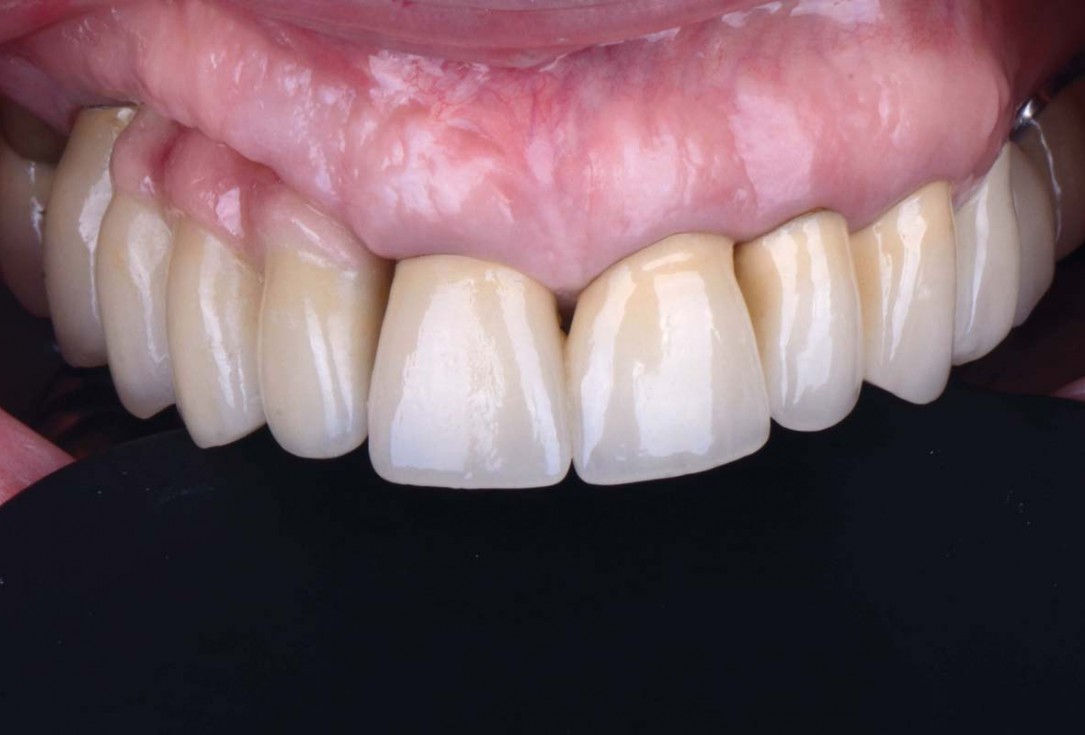

Pre-operative clinical situation: changed color in the gingiva in the front maxilla